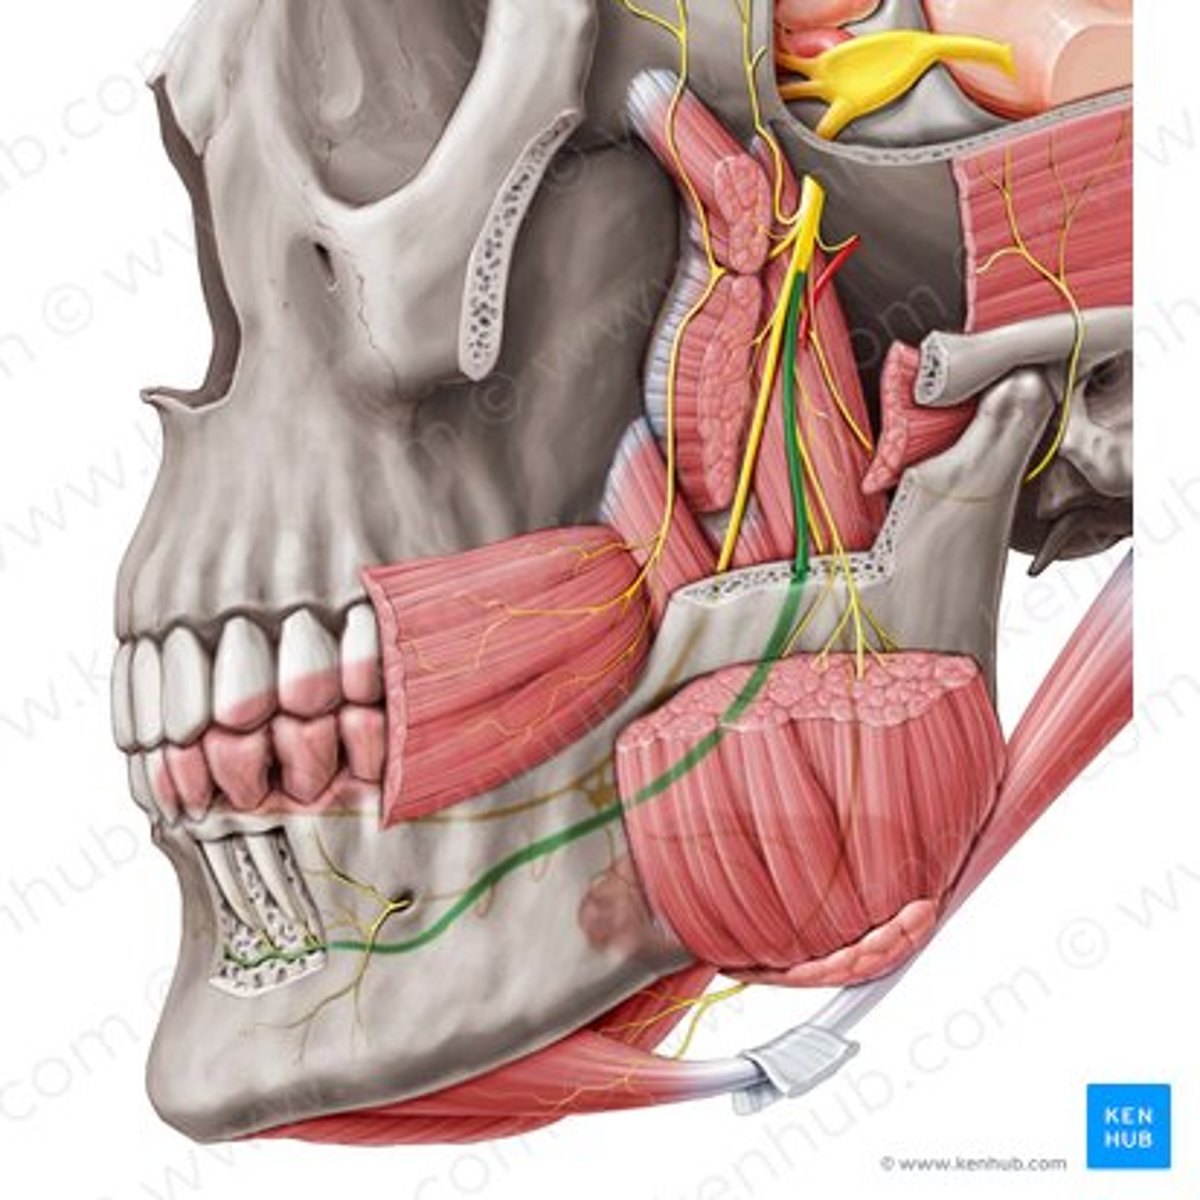

inferior alveolar nerve

inferior alveolar artery

medial pterygoid

mental nerve

lingual nerve

buccal artery

buccal nerve

mandibular foramen

buccinator